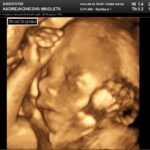

3D/4D ultrazvuk

3D/4D video a foto bábätka s najmodernejším ultrazvukovým prístrojom

vyhotovenie farebných fotiek a nahrávanie záznamov na USB kľúč/DVD